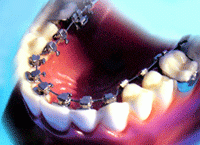

จัดฟันแบบเหล็ก (Metal Braces)

ใช้ลวดจัดฟัน และ brackets เพื่อจัดฟันให้ตรง ตามแนวที่ต้องการ